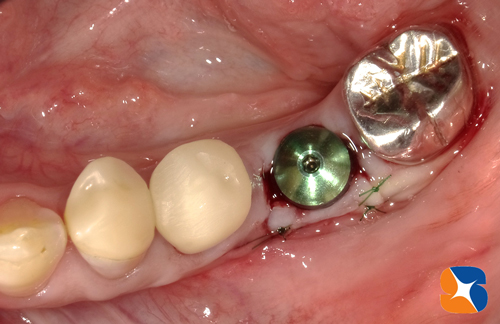

〈手術直後の写真〉

この状態のまま、約3ヶ月ほど骨とインプラント体が定着するのを待ちます。

インプラントの周囲にCGFと絡めた一塊の人工骨を添加させます。この人工骨はやがて消失され、本物の骨に置き換わります。